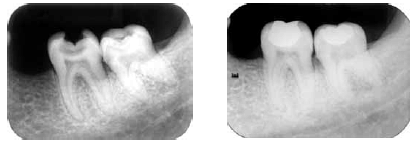

Julgue os itens a seguir acerca das radiografias acima, que mostram a preservação, após dois anos de um tratamento.

As imagens não apresentam falhas associadas ao tratamento de restauração realizado.

A câmara pulpar do dente 38 reduziu de tamanho.

É possível observar que os nódulos de calcificação pulpar do dente 37 estão progredindo.